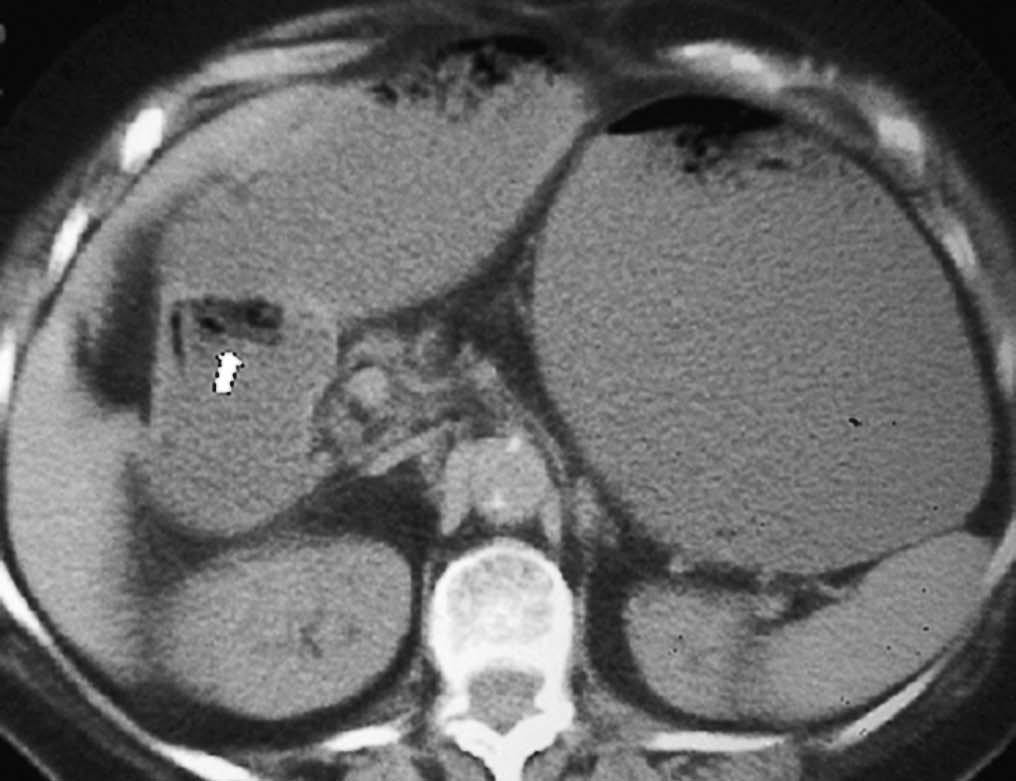

Fig. 18--Neurofibromas. (A) Ecografía. (B) Tomografía computarizada con contraste intravenoso en un paciente con enfermedad de von Recklinghausen. Se observan múltiples lesiones sólidas (*) en la pared duodenal (D). P: Páncreas.

Los tumores estromales benignos (leiomiomas) representan las neoplasias intestinales sintomáticas más frecuentes entre la patología duodenal benigna. Pueden ser intra o extraluminales, con tendencia a la ulceración y al sangrado. En la TC se observan como lesiones redondeadas, de pequeño tamaño, con captación homogénea de contraste1,22. Los lipomas intestinales aparecen como lesiones intraluminales ovoideas, homogéneas, presentando por su componente graso un bajo coeficiente de atenuación en la TC, entre 40 a 100 UH22 (fig. 16). Los adenomas son masas intraluminales de morfología variable. De entre ellos el adenoma velloso puede malignizar. Normalmente asienta próximo a la papila, por lo que con frecuencia produce obstrucción de la vía biliar con la consiguiente ictericia (fig. 17). Las poliposis familiares en ocasiones afectan al intestino delgado. Tanto la poliposis colónica familiar como el síndrome de Gardner o el síndrome de Peutz-Jeghers, además de los pólipos en el colon o en el intestino delgado, asocian adenomas en el estómago y el duodeno, con riesgo variable de degeneración a adenocarcinoma1,21,22. Los tumores neurogénicos suelen ser masas polipoideas que crecen del borde antimesentérico, siendo los más frecuentes el schwanoma y el neurofribroma. Éste puede ser único o múltiple en casos de neurofibromatosis, siendo la localización duodenal rara22,23. Radiológicamente se identifican como masas intra o extraluminales difíciles de diferenciar de leiomiomas (fig. 18).